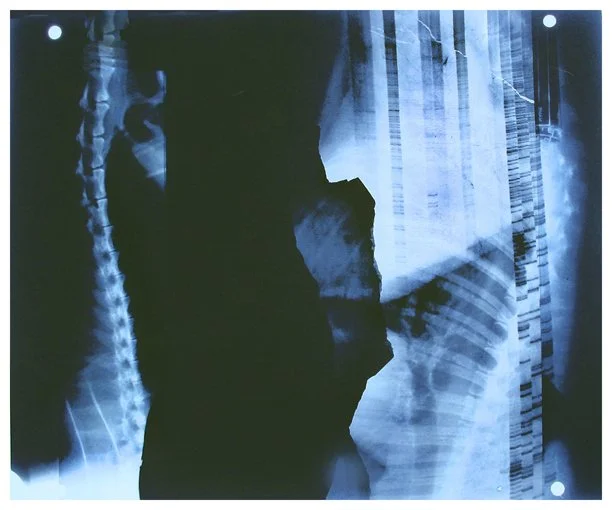

Insight is a series of collaged X-ray fragments, which were digitally composed into giclée prints. They speak not only of the body’s interior, but of the human experience it contains.

Drawn from DNA sequencing gels, mammograms, ultrasound scans, and cell cultures grown in Petri dishes, these compositions reframe diagnostic materials as metaphoric landscapes. What once served to identify illness becomes a language of line, texture, and light. They serve as a quiet meditation on fragility, resilience, and the unseen forces that shape us.

Each image in Insight is both an anatomical artifact and an artistic inquiry. Each one is part of my ongoing exploration of the relationship between Art, Science, and Medicine. Through digital layering and compositional play, I aim to dissolve the boundary between clinical detachment and emotional intimacy by inviting viewers to look inward and find meaning in the microscopic.